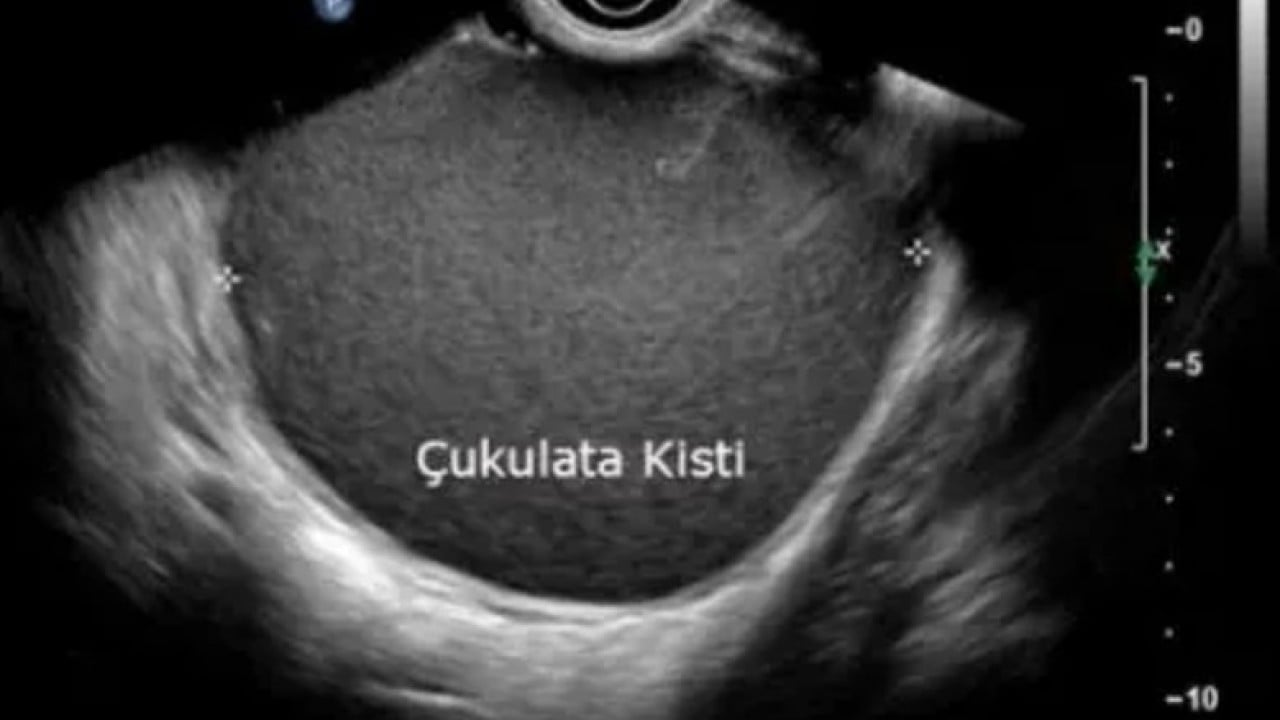

Prof. Dr. Gürkan Bozdağ, halk arasında "çikolata kisti" olarak bilinen endometriozisin her 10 kadından birini etkilediğini, belirtilerinin farklı hastalıklarla karışabilmesi nedeniyle tanının gecikebildiğini söyledi.

Türk Üreme Sağlığı ve İnfertilite Vakfı (TFRM) Başkanı Prof. Dr. Gürkan Bozdağ, şiddetli adet sancısı, kronik pelvik ağrı ve kısırlığa kadar uzanan önemli sağlık sorunlarına yol açabilen kronik bir hastalık olarak nitelendirilen endometriozise ilişkin bilgi verdi.

Endometriozisin belirtilerinin farklı hastalıklarla karışabilmesi nedeniyle tanısının gecikebildiğini vurgulayan Bozdağ, bu sürecin dünya genelinde 7-10 yıl sürdüğünü söyledi. Hastalığın sessiz ilerlemesinin en önemli nedenlerinden birinin toplumsal algı olduğuna dikkati çeken Bozdağ, şiddetli adet ağrısının çoğu zaman kabul edildiğini kaydetti.

Endometriozisin çoğu zaman geç fark edilen, belirtileri başka hastalıklarla karışabilen ve tanısının yıllarca gecikebilen bir kadın sağlığı sorunu olduğunu belirten Bozdağ, "Tanı sürecinde uzman değerlendirmesi çok önemlidir. Görüntülerdeki küçük, silik ya da gözden kaçabilecek bulgular her zaman kolay fark edilmeyebilir." dedi.

Bozdağ, yapay zekanın tam da bu noktada önemli fark yaratabileceğine işaret ederek, bu sistemlerin MR ve ultrason gibi görüntülemelerde insan gözünün atlayabileceği ince işaretleri daha hızlı ve daha sistematik biçimde analiz edebileceğini kaydetti.